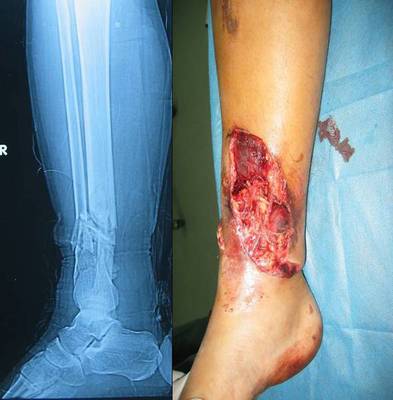

小腿骨折打钢钉图片,骨折钢钉露在外面图片

脚踝骨折 十一个钢钉 术后一个月就能走路了.

右足踝骨骨折已做钢钉内固定手术有120天了,为什么现在走路足踝骨还是

打钢钉和钢板的小腿x光图像图片

左小腿腓骨胫骨骨折,钛合金在体内.现在还躺医院没出院!

24岁左胫骨腓骨远端骨折及pillon骨折康复记录有手术刀口图片比较血腥

骨折钢钉露在外面图片

小腿胫骨骨折微创钢钉

骨折打钢钉图片